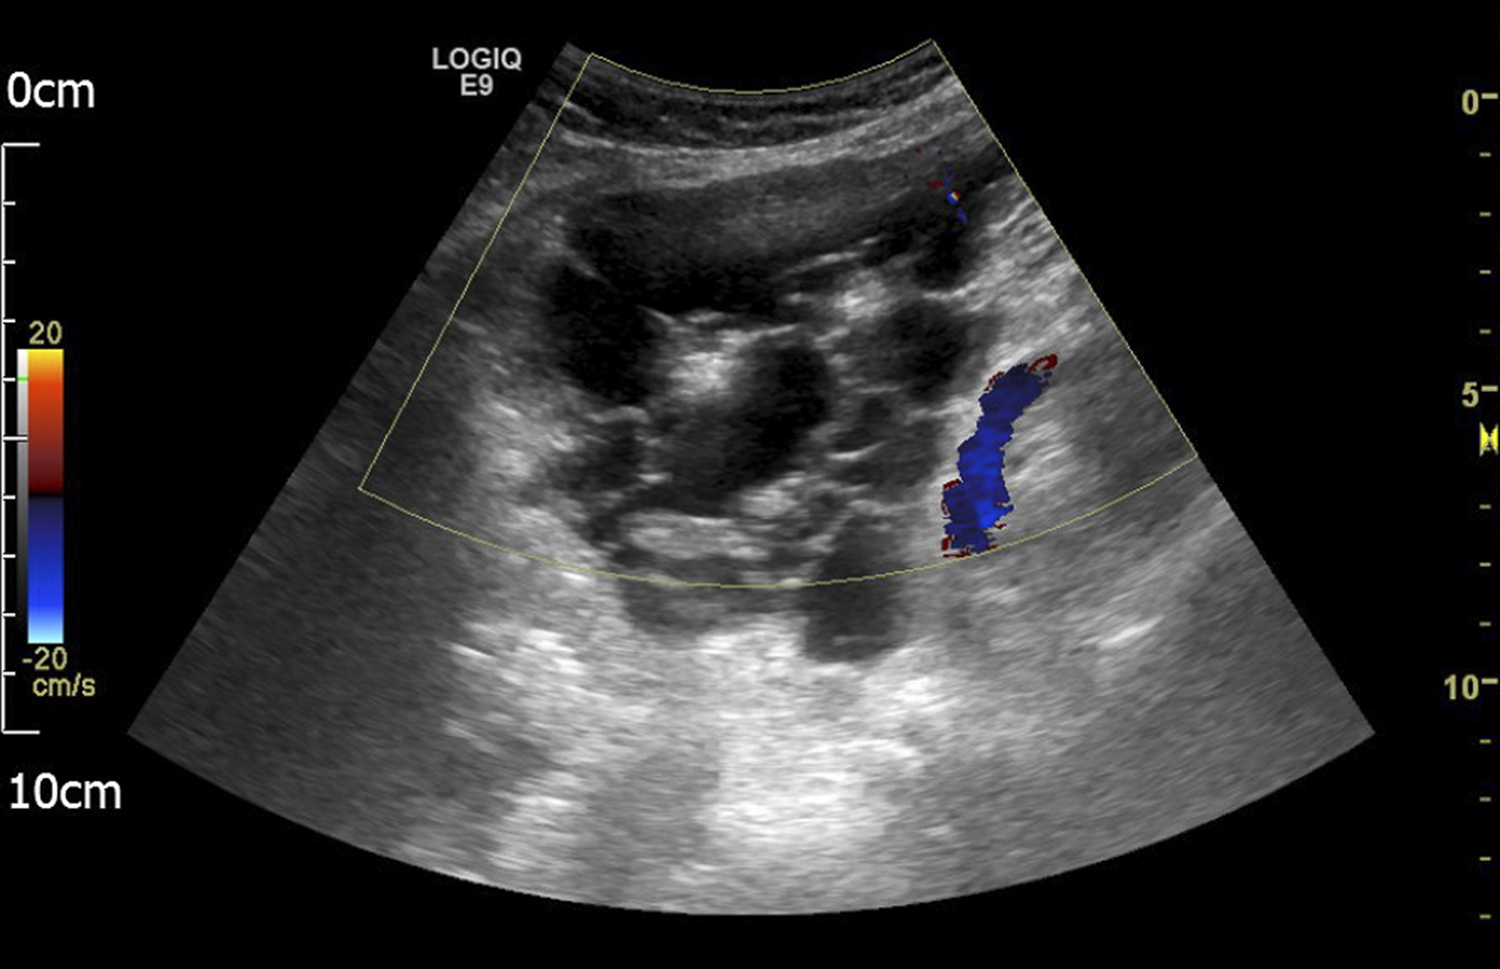

Mesothelioma peritoneal mesothelioma, diagnostic test: Peritoneal mesothelioma is a very rare diagnosis with an incidence of 1 case per. Studding the peritoneum and serosa of the small bowel at surgery. The ultrasound examiner entertained a diagnosis of mucinous borderline ovarian tumor of intestinal type, even if the small dimensions of the . Diagnosis is confirmed histologically on . Abdominal mass was noted leading to ultrasound and subsequent ct scans. Of peritoneal mesothelioma representing the following histologic. Sometimes ultrasound (or an echocardiogram) is used to guide the needle. Standard ct imaging diagnostic test: In cases of peritoneal mesothelioma, fluid can build up in the. Benign multicystic peritoneal mesothelioma (bmpm) is a rare condition, more common in. Ultrasound (us) and, above all, ct scan are useful for diagnosis. An abdominal ultrasonogram when taken revealed a right subphrenic heterogeneous mass with cystic and solid portions, limited by an irregular .

Abdominal mass was noted leading to ultrasound and subsequent ct scans. Malignant peritoneal mesothelioma is an uncommon primary tumor of the peritoneal lining. An abdominal ultrasonogram when taken revealed a right subphrenic heterogeneous mass with cystic and solid portions, limited by an irregular . Ultrasound (us) and, above all, ct scan are useful for diagnosis. Standard ct imaging diagnostic test: